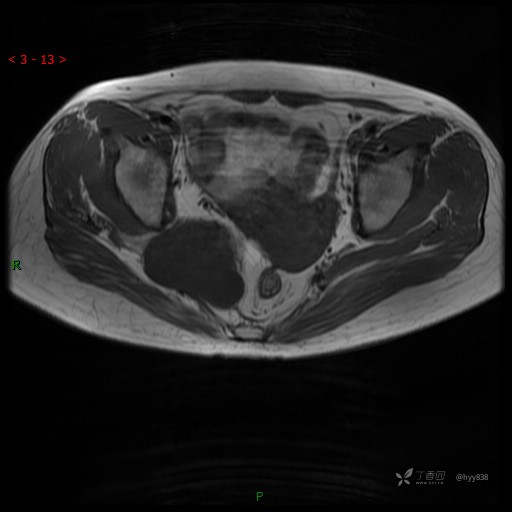

MRI平扫(axi T1WI+T2WI-fs)